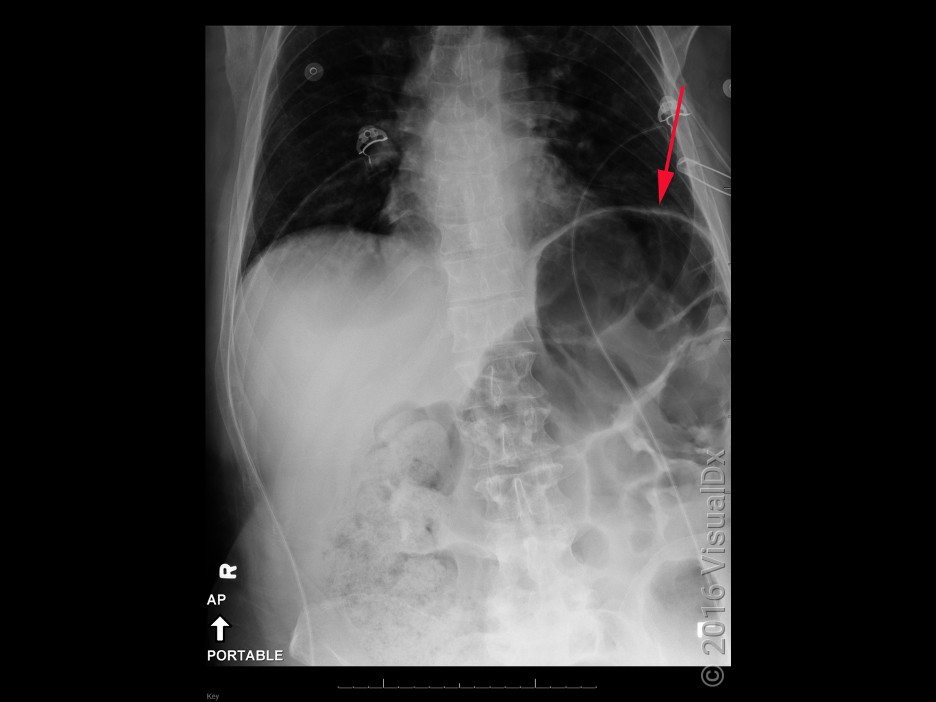

VisualDX_LargeBowelObstructionImage